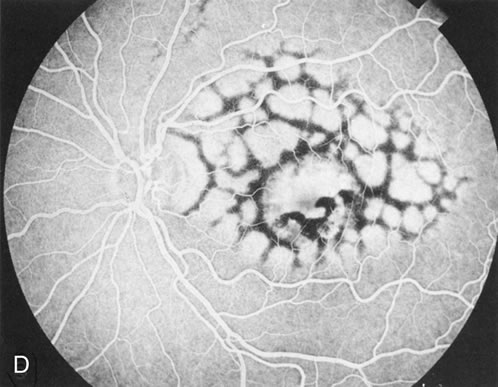

There is no clear agreement as to what constitutes dominantly inherited drusen and what constitutes age-related degenerative drusen. There is a distinct group of younger individuals with bilateral, symmetric, uniformly small, round, discrete, yellow and white drusen. Histopathology demonstrates a nodular thickening of the RPE basement membrane, and these drusen have therefore been referred to as basal laminar, or cuticular, drusen.24

FA shows a characteristic pinpoint area of transmission hyperfluorescence corresponding to the drusen and reveals many more than are appreciated clinically (Fig. 12). Secondary changes such as pigment atrophy and dispersion, exudative and nonexudative detachments, and occasionally a neovascular membrane, will be revealed by FA (Fig. 12E).

Fig. 12. Dominant drusen of Bruch's membrane. The drusen appear as yellowish-white “blisters” predominantly in the temporal posterior pole (A). The angiogram shows many pinpoint areas of transmission hyperfluorescence typical of drusen, some of which have coalesced to form broader areas of hyperfluorescence (B). These drusen occasionally result in ingrowth of a choroidal neovascular membrane, such as occurred in this case over a 5-year period (C–E).